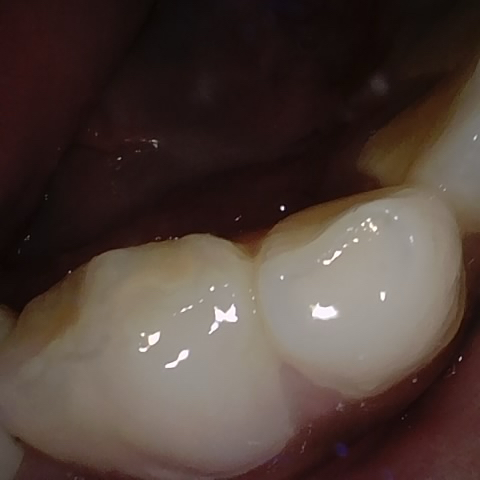

Annotated as "Good"